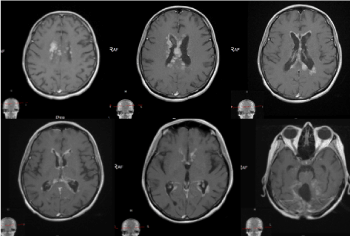

Figure 9. SAG T1, AX T2, AX T2 FLAIR and COR T2 FLAIR, 3DT1+C MR postcontrast images of the cerebrum without the presence of leptomeningeal metastases

The control MRI of the cerebrum/20.08.13.

Conclusion

MRI data on mild internal hydrocephalus. No evidence of tumour relapse or areas of suspicion for leptomeningial metastases. Treatment was discontinued and monitoring was assessed in 3-months. Three months of a control MRI of the cerebrum and spinal axis: multiple nodules with leptomeninigial localization, hyperintensity T2 and an intensity enhancing signal after contrasting are visualized. The nodules are located on the right parietal area with a diameter of 8 mm; To the right occinpitally 14 mm in diameter; Several small nodules occipital, parasagittal with a diameter of up to 4.5 mm.; To the right frontal parasagittal with a diameter of 7 mm.; In front of the upper part of the vermis, dorsal from lamina quadrigemina 11 mm in diameter. Symmetric slightly dilatable ventricular system of low- dimensional dynamics compared to the previous study. Extended and deformed IV-th ventricle. A single nodule with leptomeningeal localization is visualized along the ventral surface of the cervical myelon.

MRI data on multiple leptomeningial metastases, with no evidence of local relapse. Since 07.12.13, the child conducts 3 cycles of the second line of the SC with Temozolomide 120 mg/day in 5 days courses. The control MRI of the cerebrum/ 18.02.14г. - Multiple leptomeningeal metastases. From 28.02.14, the child continues with 2 more courses of SC with Vincristine, Carboplatinum and Etoposide. The control MRI of the cerebrum/23.04.14 - Without significant dynamism. In May 2014, manifests throat symptomatology as a result of increased intracranial pressure. MRI examination of the cerebrum of 03.07.14, without significant dynamics in the images compared to the previous study (Figure 10). After one month the outcome is exitus letalis.

Figure 10. А/ SAG T1 МR image shows the postoperative changes in the PCF, condition after surgery and extirpation of the medulloblastoma; B/ COR T2 FLAIR after contrast МR image through IV ventricle with multiple hyperintense leptomeningeal liquid metastases, predominantly infratentorial lesions; С/ 3DT1+C МR postcontrast image with multiple contrast-enhancing leptomeningeal metastases on folia cerebelli